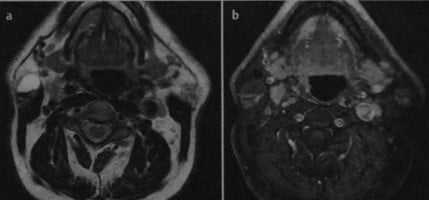

![Снимки МРТ и КТ. Опухоль Уортина]()

В горизонтальной проекции наблюдается высокая интенсивность сигнала переднего кистозного компонента на Т2-взвешенном изображении (а) и низкая интенсивность сигнала на Т1 -взвешенном изображении после введения гадолиния (b). Солидный задний компонент усиливается на Т1 -взвешенном изображении (b).